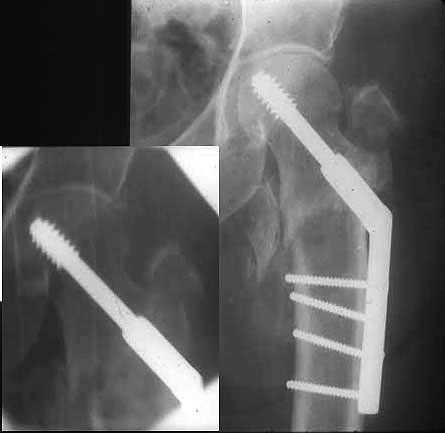

Это 4-фрагментный перелом, традиционно-современная фиксация - это динамический бедренный винт, DHS. Либо какой-либо из проксимальных бедренных гвоздей, предназначенных для ранней полной нагрузки, из-за меньшего доступа, других преимуществ перед DHS нет. Если доступен только реконструкционный гвоздь, то винты вводить надо очень точно и аккуратно субхондрально, т.е. максимальной длины, а то прорежутся в головке.

Вот пример наших американских коллег про DHS. Видно, как стелескопировались отломки, хотя поначалу был оставлен диастаз.

Фиксатор или DHS 130 градусов или PFN с короткой ножкой. Если DHS, то шуруп должен находиться в центре шейки и дополнительно еще простой длинный шуруп против ротации в проксимальной части шейки над шурупом DHS. Полную нагрузку на ногу начать через 6 недель.